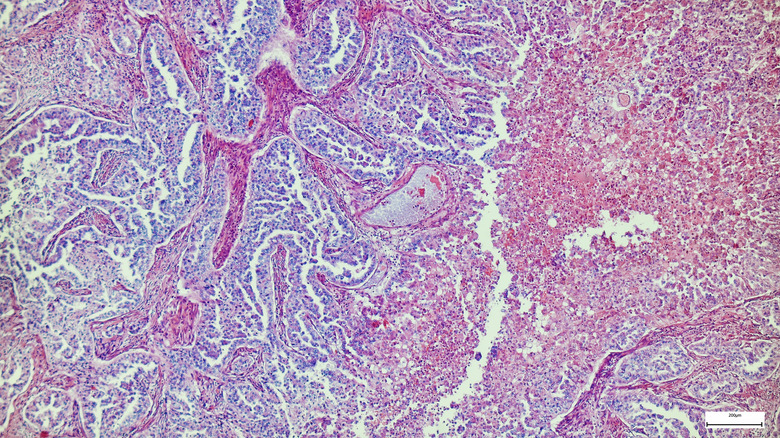

In a trial run by Verve Therapeutics, a Cambridge–based biotech company, researchers discovered that a single infusion of a gene-editing treatment called VERVE-101 was able to reduce cholesterol levels in patients. This treatment was tested in individuals with hereditary conditions that made them susceptible to developing clogged arteries and heart attacks. Scientists were able to use CRISPR editing techniques to tweak liver gene cells. The researchers "turned off" a cholesterol-raising gene called PCSK9, which is found in the liver, in order to lower LDL-C — sometimes called "bad" cholesterol — which causes plaque to build up in arteries in the first place.